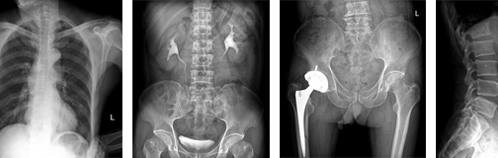

三、用途

本機為組合式X射線攝影醫(yī)療診斷設備,適用于病房、急診室、手術室、ICU、放射式等處對人體的頭部、四肢、胸腔、腰腹等多部位進行攝影的移動式診斷設備。